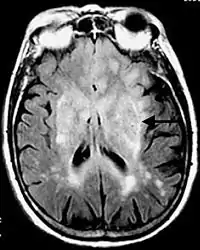

![]() La imagen de RM ponderada en T2 muestra (en el lado derecho) la infiltración difusa del tumor. | ||

En las imágenes de resonancia magnética, el tumor aparece como una lesión difusa, poco circunscrita, infiltrante y sin captación de contraste, con señal hiperintensa en las imágenes ponderadas en T2, y que se expande hacia la materia blanca. Puede ser difícil de distinguir de un astrocitoma anaplásico altamente infiltrante o un glioblastoma.[6]

La característica radiológica más frecuente en la RM es la infiltración en forma de lesión hiperintensa en T2 y FLAIR tanto de la sustancia blanca como de la sustancia gris. Con la administración de contraste el realce es mínimo o ausente.[14][15]